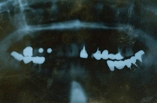

◎初診時の状態 ・右上の奥歯がぐらついて、入れ歯が入れにくい ・入れ歯で噛むと痛む ◎患者様の希望 ・上の入れ歯がかさばるので、インプラントをしてもらいたい |

| 【治療内容】 上のぐらついた歯を抜歯し、歯ぐきの状態が安定した後に手前の無い2本と共にインプラントを入れました。 その後、左下の奥歯も歯周病で噛めない箇所があったため、抜歯後インプラント、前装クラウンを右上、左下共に装着しました。 |